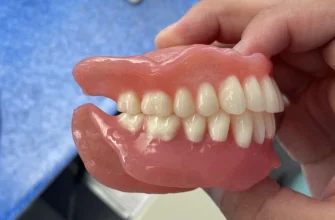

Тип протеза

Различные типы протезов имеют разный срок службы. Например, съемные протезы требуют более тщательного ухода и, как правило, имеют меньший срок службы, чем несъемные. Имплантаты, в свою очередь, при правильном уходе могут прослужить десятки лет. Выбор типа протеза должен осуществляться совместно с врачом-ортопедом, с учетом индивидуальных особенностей пациента и его финансовых возможностей.

| Съёмные пластиночные протезы | 5-7 лет | Качество материалов, гигиена полости рта, привычки пациента |

| Съёмные нейлоновые протезы | 7-10 лет | Качество материалов, гигиена полости рта, привычки пациента |